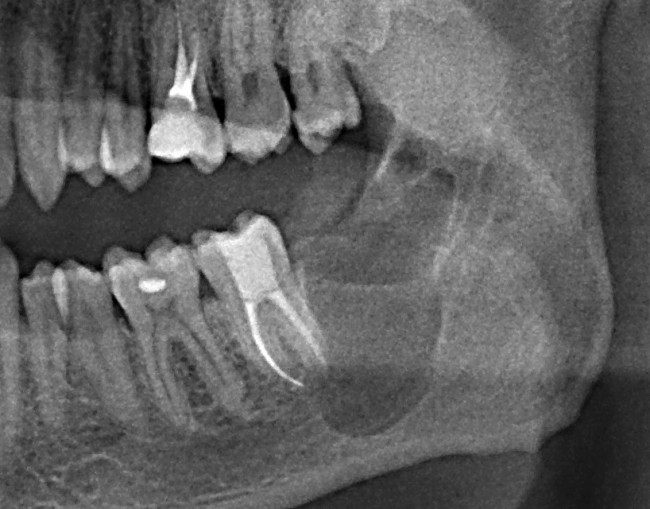

К нам в клинику обратился молодой человек с целью плановой санации: почистить зубной налет, вылечить кариес и т. д. Перед лечением ему сделали панорамный снимок. На снимке вот это:

1

Напомню, он пришел с целью плановой санации, а это значит, что ни зуб мудрости, ни киста. ни что-то там еще его не беспокоят. А теперь, внимание, вопрос ко всем вам:

Вернусь к нашему клиническому случаю. Да, ни зуб мудрости, ни киста, которая из-за него возникла, нашего пациента не беспокоят. Тем не менее, все вы видите явные показания к удаления и ретинированной восьмерки, и кисты.

Что мы и делаем. До удаления я попросил нашего терапевта Михайлову Елену депульпировать соседний седьмой зуб, поскольку, по данным КЛКТ, его корни выходили в просвет кисты. Жалко, конечно. Но вот, такие коварные эти зубы мудрости.